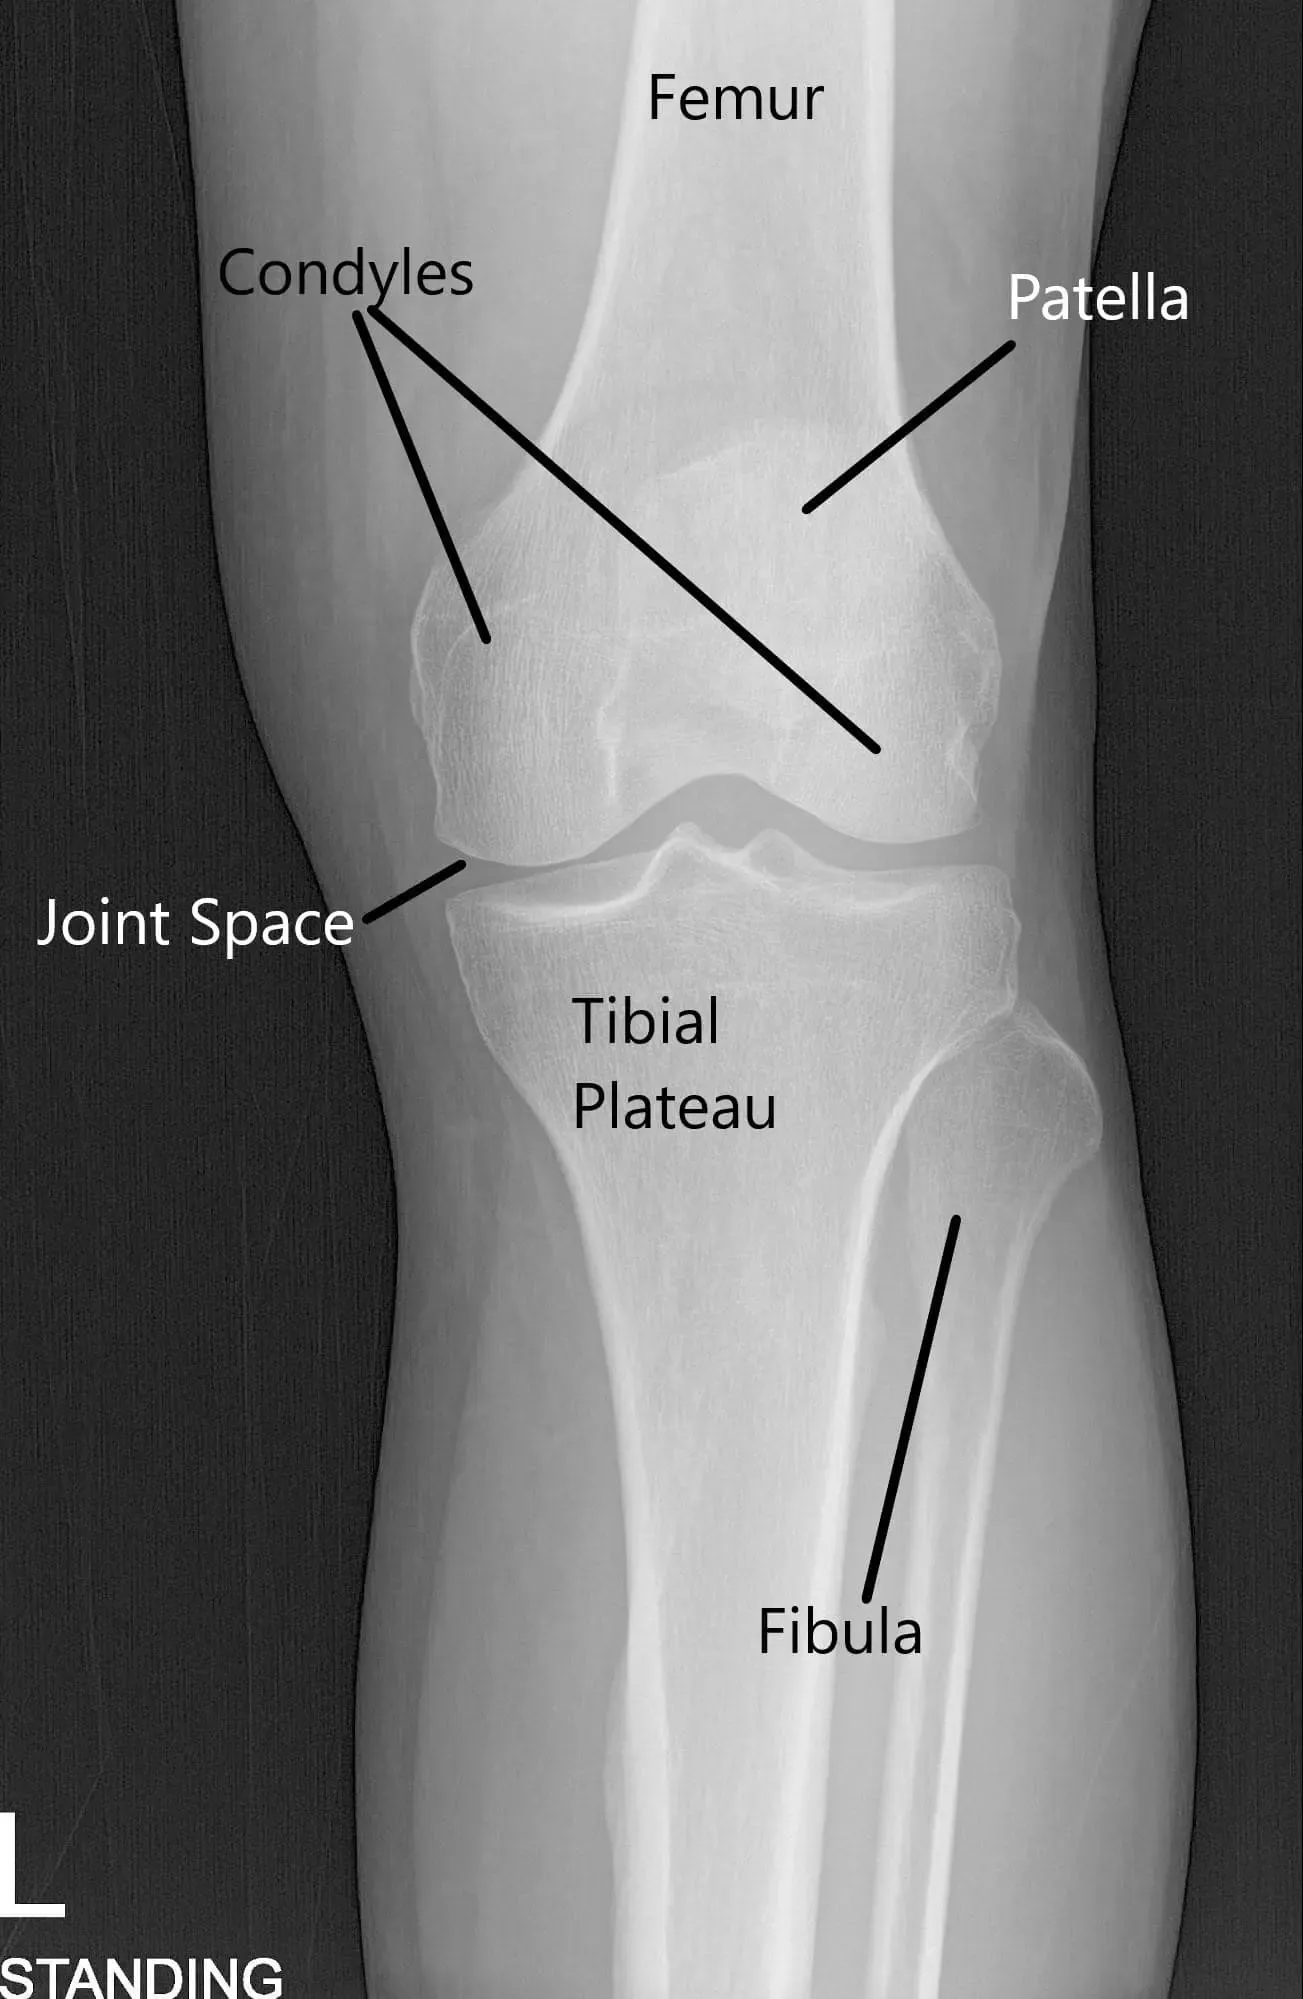

Radiografía de la rodilla en vista AP y skyline.